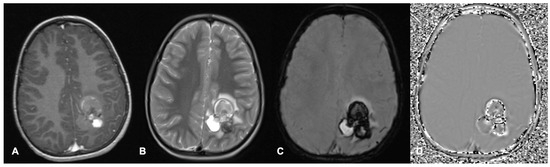

| SWI | Susceptibility-weighted imaging |